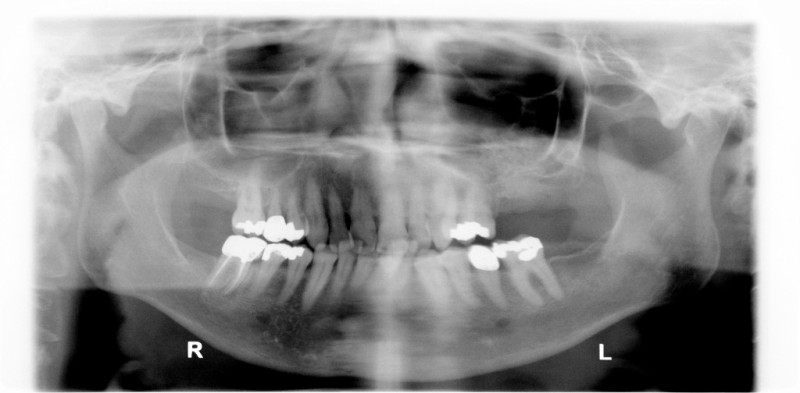

Alveolar Cleft (Defect in the Upper Jaw) Repaired with a Hip Bone Graft

After Bone Graft